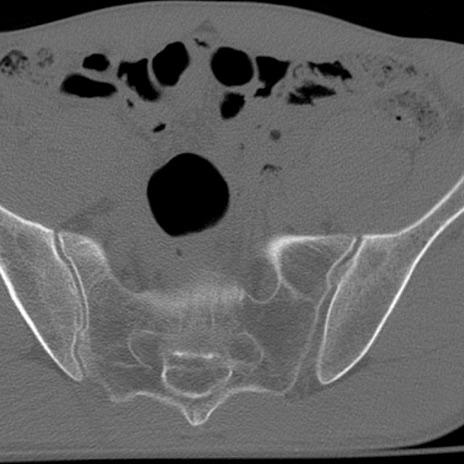

症例3 腰椎CT(横断像)

腰椎CT